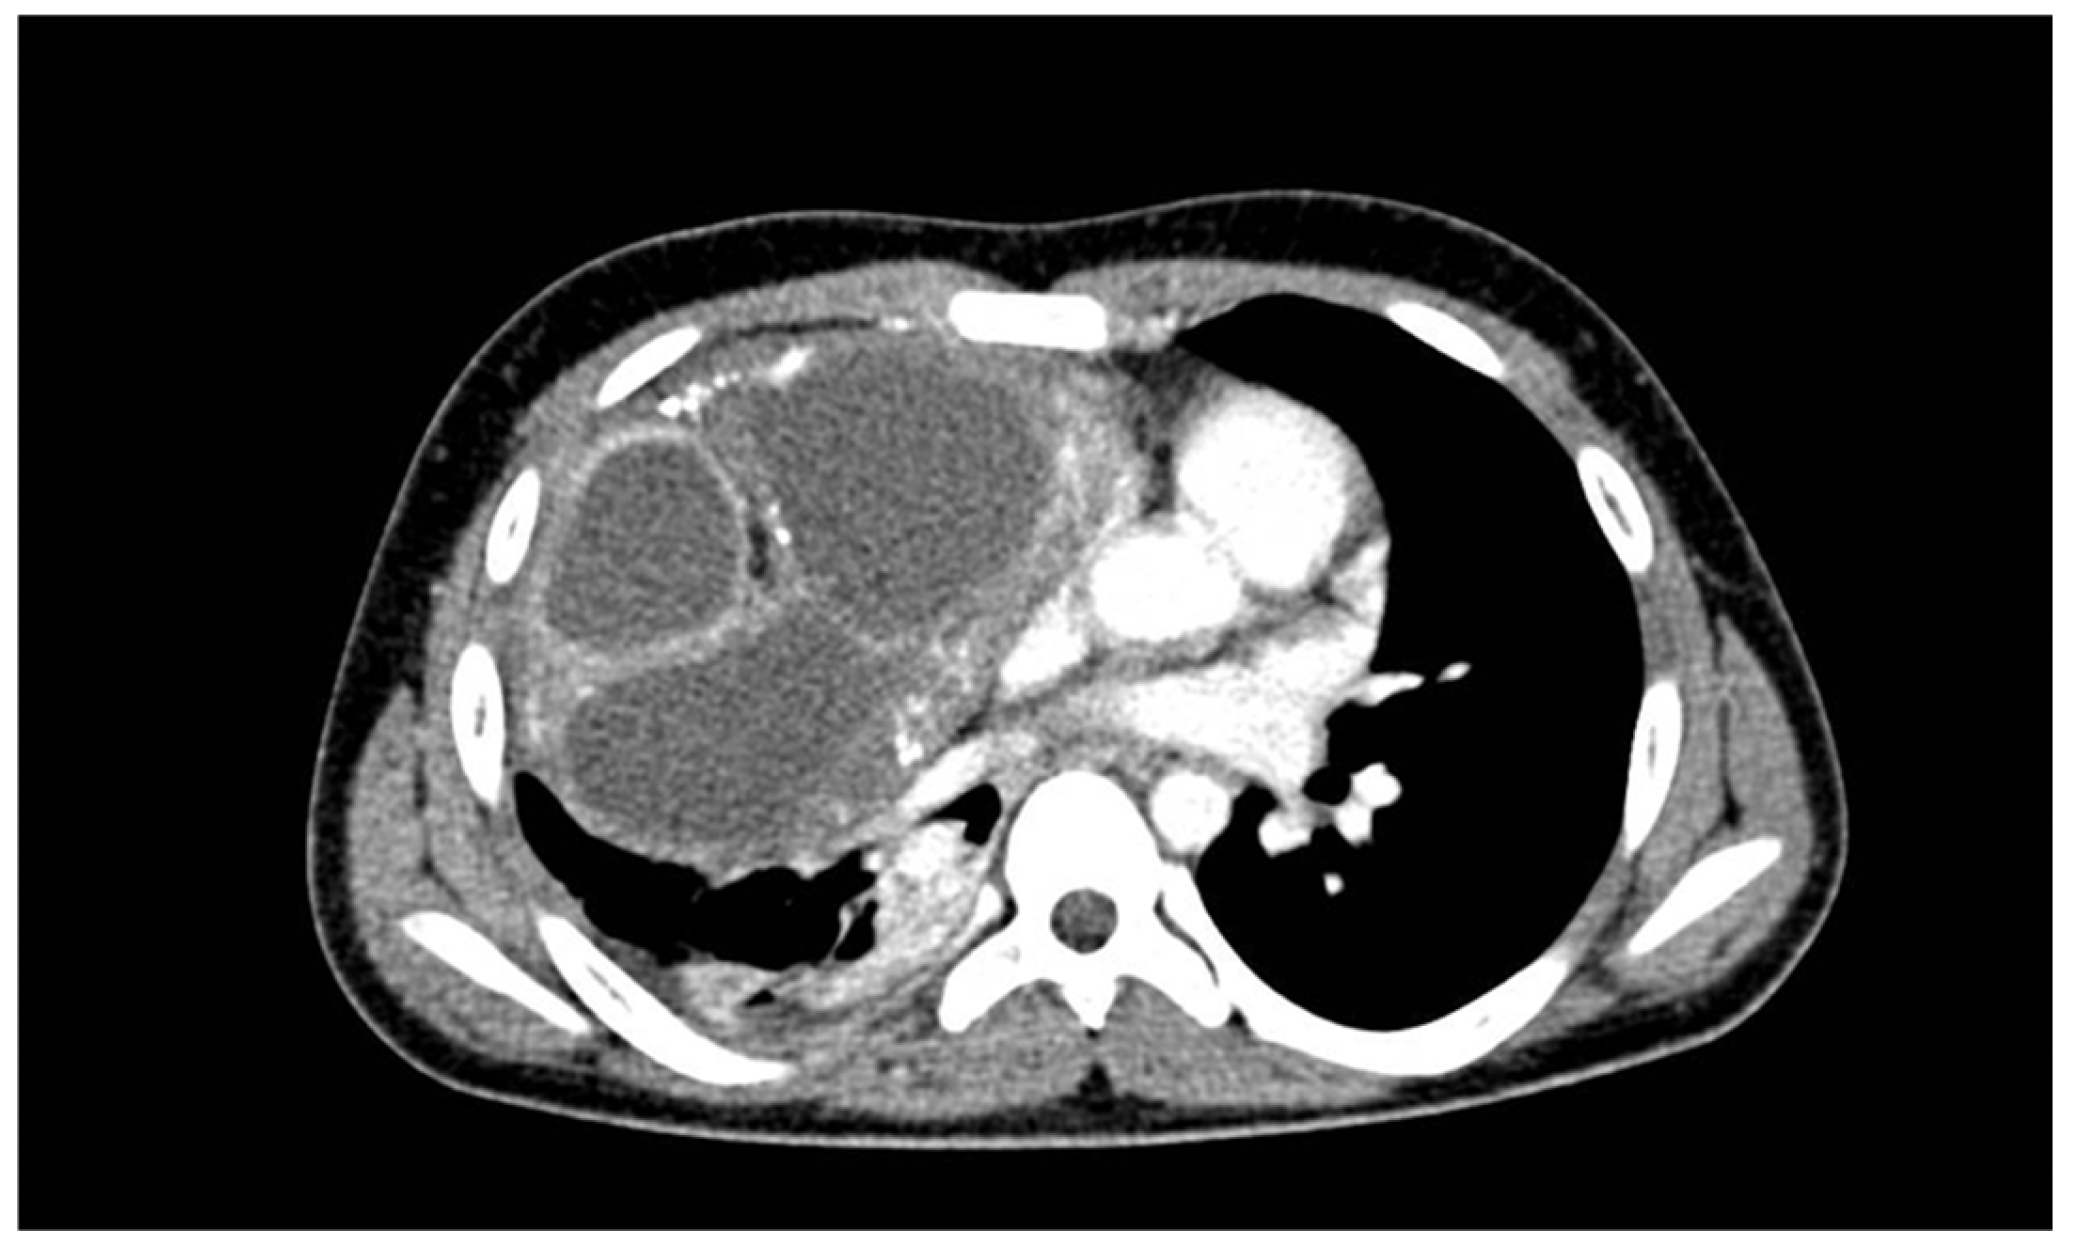

2. Case Report